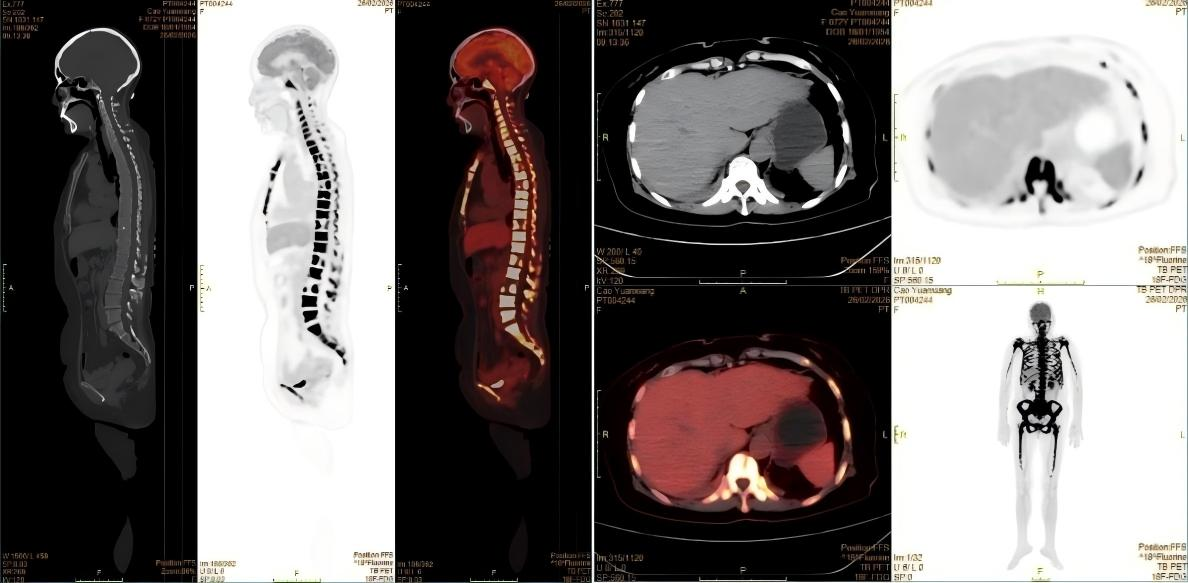

经PET-CT检查,患者全身骨弥漫性明显代谢增高,其他脏器均并未找到明确的实体原发灶,这样的显像结果推翻了肿瘤骨转移的初步诊断。核医学科医生看到这样的显像结果,并结合患者的临床表现,一个新的诊断方向在脑海中回荡:淋巴瘤?血液系统疾病?按照这一方向,为患者进一步进行了骨髓穿刺等检查,终于这个凶手被找到——急性淋巴细胞白血病。

患者PET-CT的显像图。

急性淋巴细胞白血病是一种起源于淋巴细胞的恶性肿瘤,其异常增生的白血病细胞会浸润全身骨骼和骨髓,破坏骨代谢平衡,导致骨骼出现弥漫性代谢活跃和浓聚表现。这正是患者在PET-CT和骨扫描上出现异常浓聚的原因。同时,患者持续发热、体重骤降等症状,也是白血病细胞大量增殖、释放致热原并抑制机体正常免疫功能的典型表现。